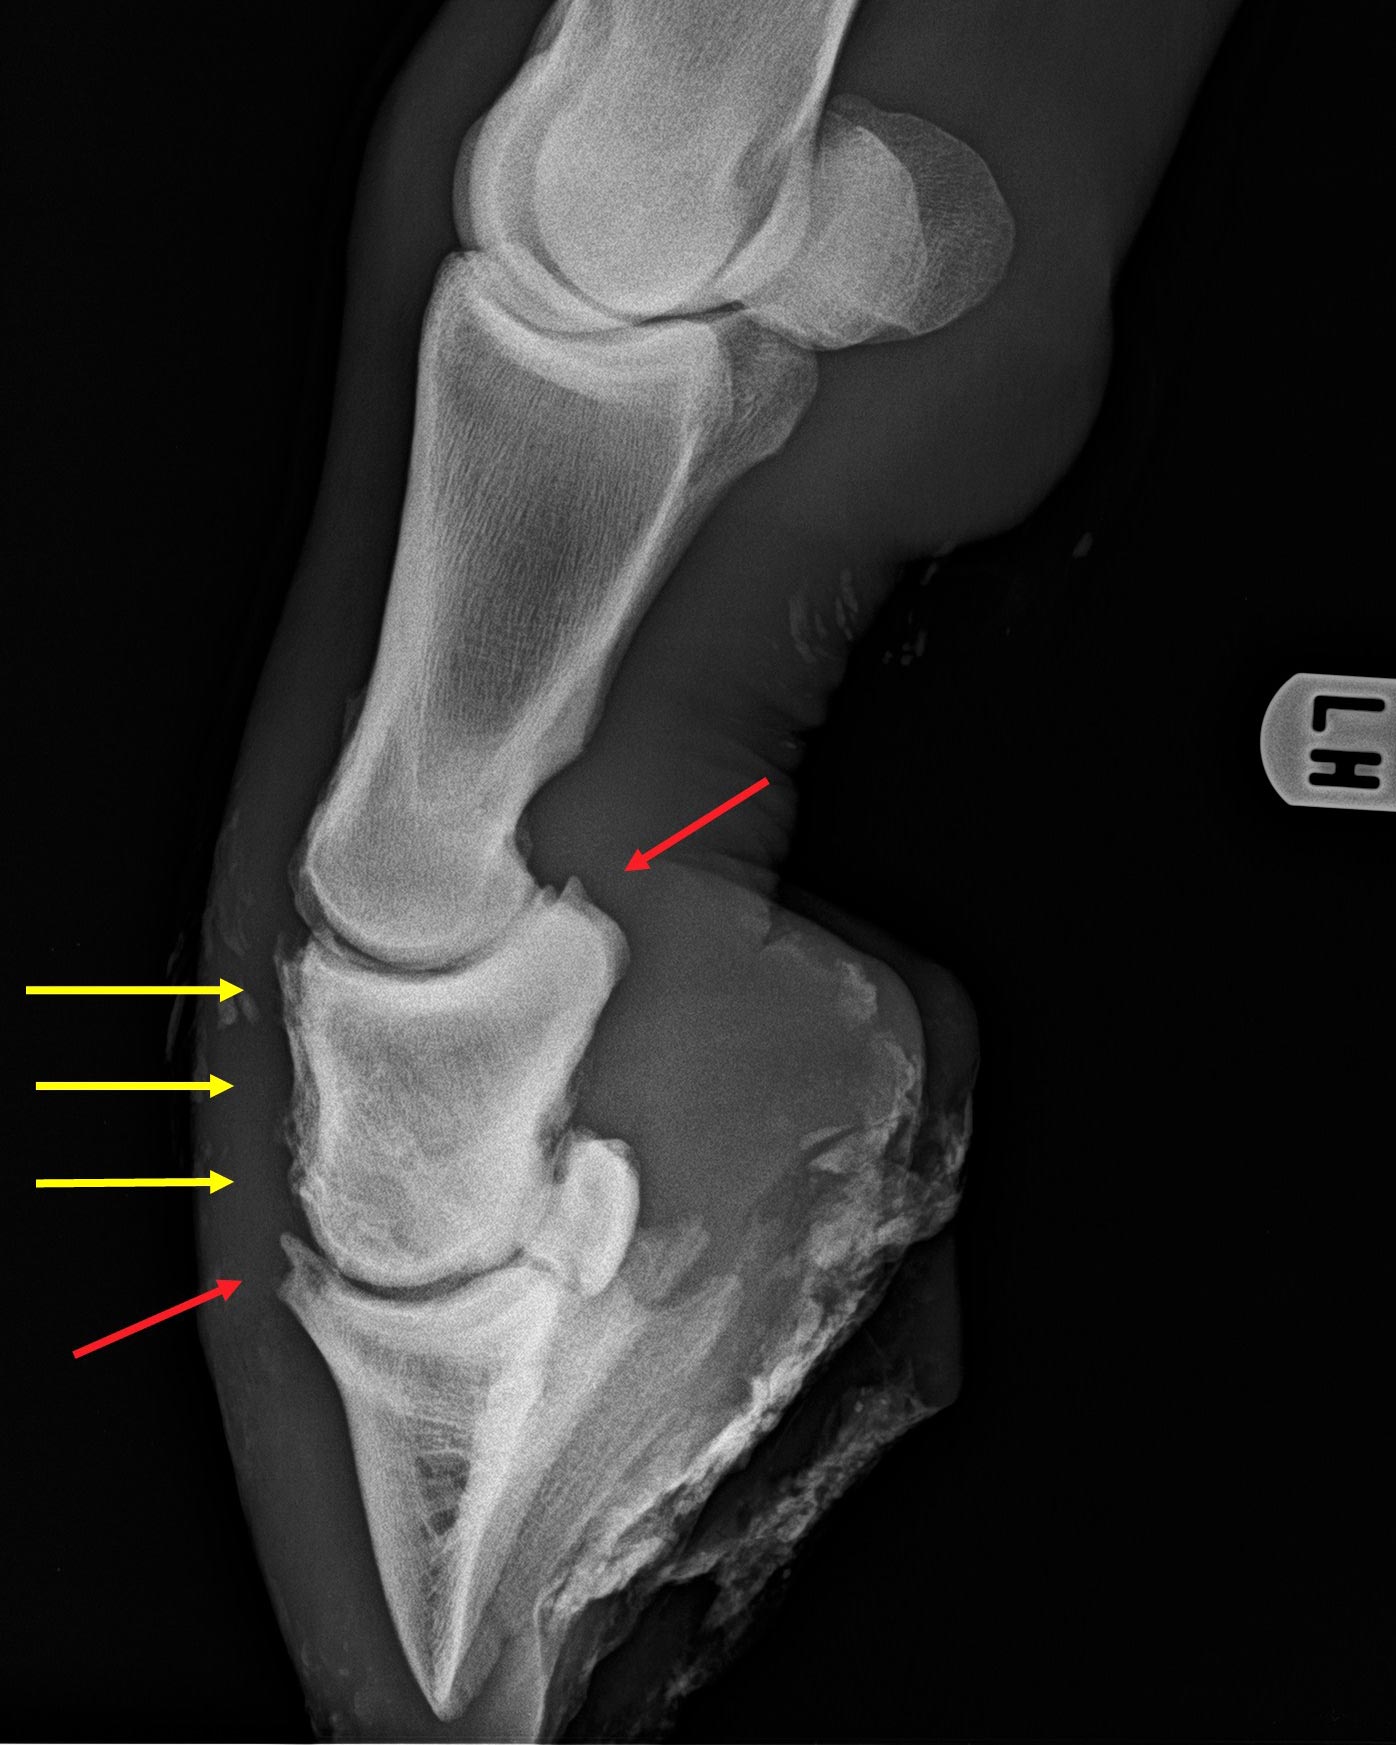

Hinterzehe eines Pferdes mehrere Jahre nach einer Kronbeinfraktur

Kron- und Hufgelenkarthrosen (rote Pfeile) und knöcherne Zubildungen auf dem Kronbein (gelbe Pfeile)